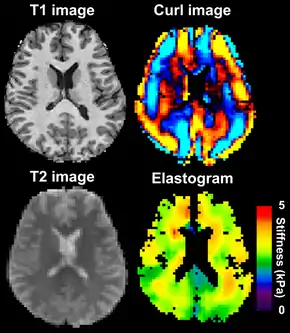

![]() Magnetic resonance elastography of the brain. A T1 weighted anatomical image is shown in the top-left, and the corresponding T2 weighted image from the MRE data is shown in the bottom-left. The wave image used to make the elastogram is shown in the top-right, and the resulting elastogram is in the bottom-right. | |

MRE is conducted in three steps: first, a mechanical vibrator is used on the surface of the patient's body to generate shear waves that travel into the patient's deeper tissues; second, an MRI acquisition sequence measures the propagation and velocity of the waves; and finally this information is processed by an inversion algorithm to quantitatively infer and map tissue stiffness in 3-D.[1][2][3] This stiffness map is called an elastogram, and is the final output of MRE, along with conventional 3-D MRI images as shown on the right.[1]